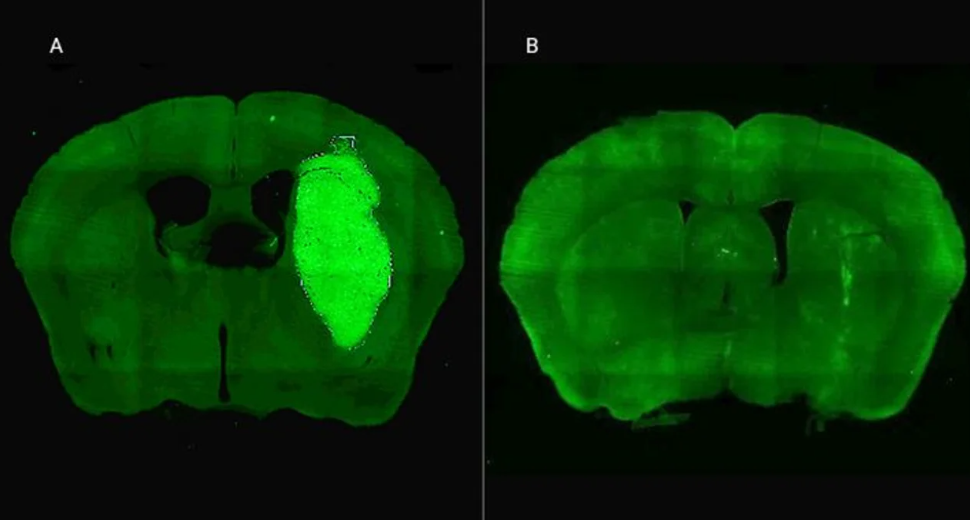

Candolfi y colegas utilizaron una terapia génica experimental basada en una molécula muy pequeña o péptido llamado P60, desarrollado por Juan José Lasarte en la Universidad de Navarra, en España, que atraviesa la membrana celular e inhibe la proteína Foxp3. “Cuando en experimentos de laboratorio bloqueamos Foxp3 utilizando P60, la respuesta de las células de glioblastoma a la radioterapia y a una variedad de drogas quimioterapéuticas mejoró notablemente”, destacó la investigadora del CONICET.

Además, P60 tuvo efectos antitumorales directos, reduciendo la viabilidad y la migración de las células de glioblastoma e inhibiendo la proliferación de células endoteliales que son clave para la progresión del tumor. Para evaluar estos efectos, los autores del estudio utilizaron una variedad de modelos celulares murinos (de roedor) y humanos. “En particular, los cultivos derivados de biopsias de pacientes con glioblastoma desarrollados por nuestro colaborador Guillermo Videla Richardson, del Instituto FLENI, son muy útiles para representar la heterogeneidad de estos tumores”, indicó Candolfi.